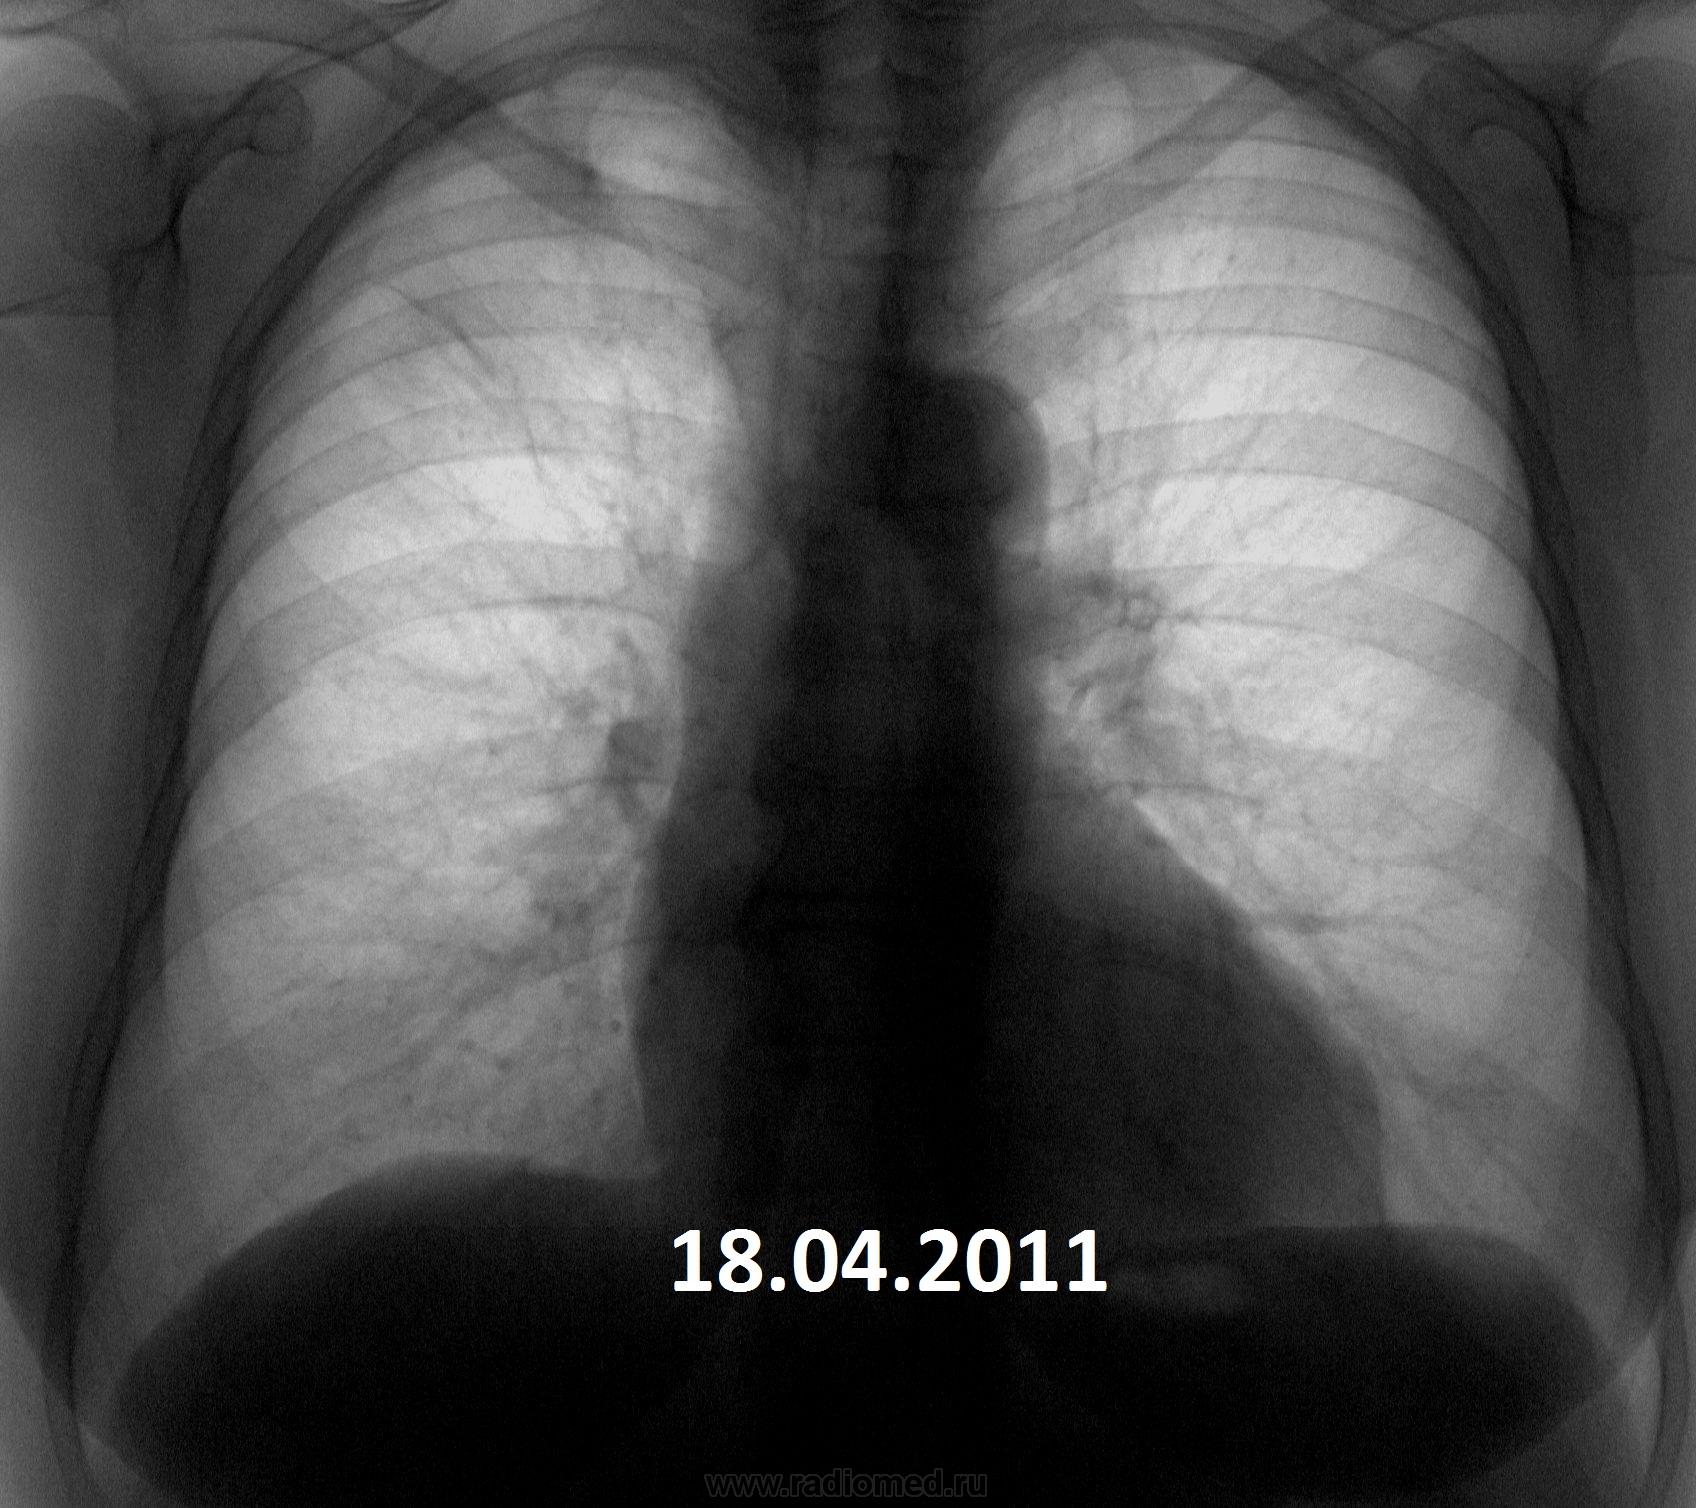

Добавлю правый бок.

1937g.r.19.03.2013_prav._bok..jpg